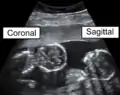

المستوى الإكليلي (بالإنجليزية: Coronal Plane) هو أحد مستويات الجسم الذي يستخدم في وصف موقع أجزاء الجسم وعلاقتها ببعضها البعض ، وهو مستوى عمودي يقسم الجسم إلى جزأين أمامي أو بطني (Anterior) و خلفي أو ظهري (Posterior) ، ويكون إسقاطه عامودياً على المستوى السهمي .